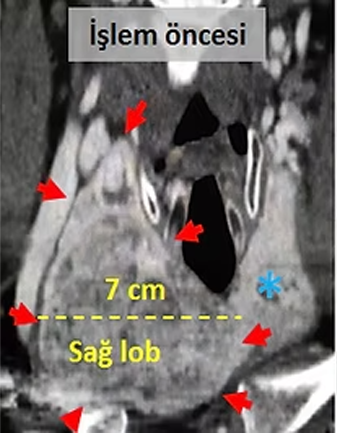

Tiroid sağ lobunda en büyüğü 7cm çaplı, göğüs boşluğuna uzanan nodüller bulunan ve nefes darlığı şikayeti olan hastada, tiroid sağ lobunu besleyen 2 atardamar embolizasyonla tıkanıyor.

Embolizasyondan 5 ay sonra çekilen kontrol tomografilerinde, embolizasyon uygulanan sağ lobun hacimsel olarak yaklaşık %80 küçüldüğü, büyük nodülün çapının 7cm den 3.7cm ye düştüğü (hacimsel olarak %86 azalma), sağlam olan sol lobun (*) büyüdüğü ve kitlelerin soluk borusuna soluk borusuna (*) yaptığı basının azaldığı izleniyor. Hastada, boyundaki şişlik ortadan kalkmış ve işlemden bir ay sonra nefes darlığı tamamen düzelmiştir.